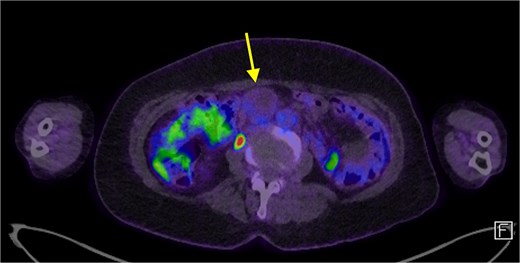

The patient’s symptoms remained stable, and she was discharged with a plan for further imaging. A fludeoxyglucose (FDG) PET scan revealed a lesion within the central mesentery with minimal FDG activity, similar to blood pooling (Fig. 2). There was a small region of mild FDG uptake at the posterior margin of the lesion, possibly representing a mural nodule. Magnetic resonance imaging (MRI) of the abdomen revealed a well-defined T2 hyperintense cystic mass with multiple thick internal septations in the small bowel mesentery measuring 31 × 33 × 34 mm. (Fig. 3) Diagnoses included centrally necrotic pathological mesenteric node, cystic/necrotic neoplasm, cystic vascular, or lymphatic abnormality or infective pathology.

A FDG PET scan in axial view demonstrating a minimally FDG avid lesion in the small bowel mesentery (arrow).